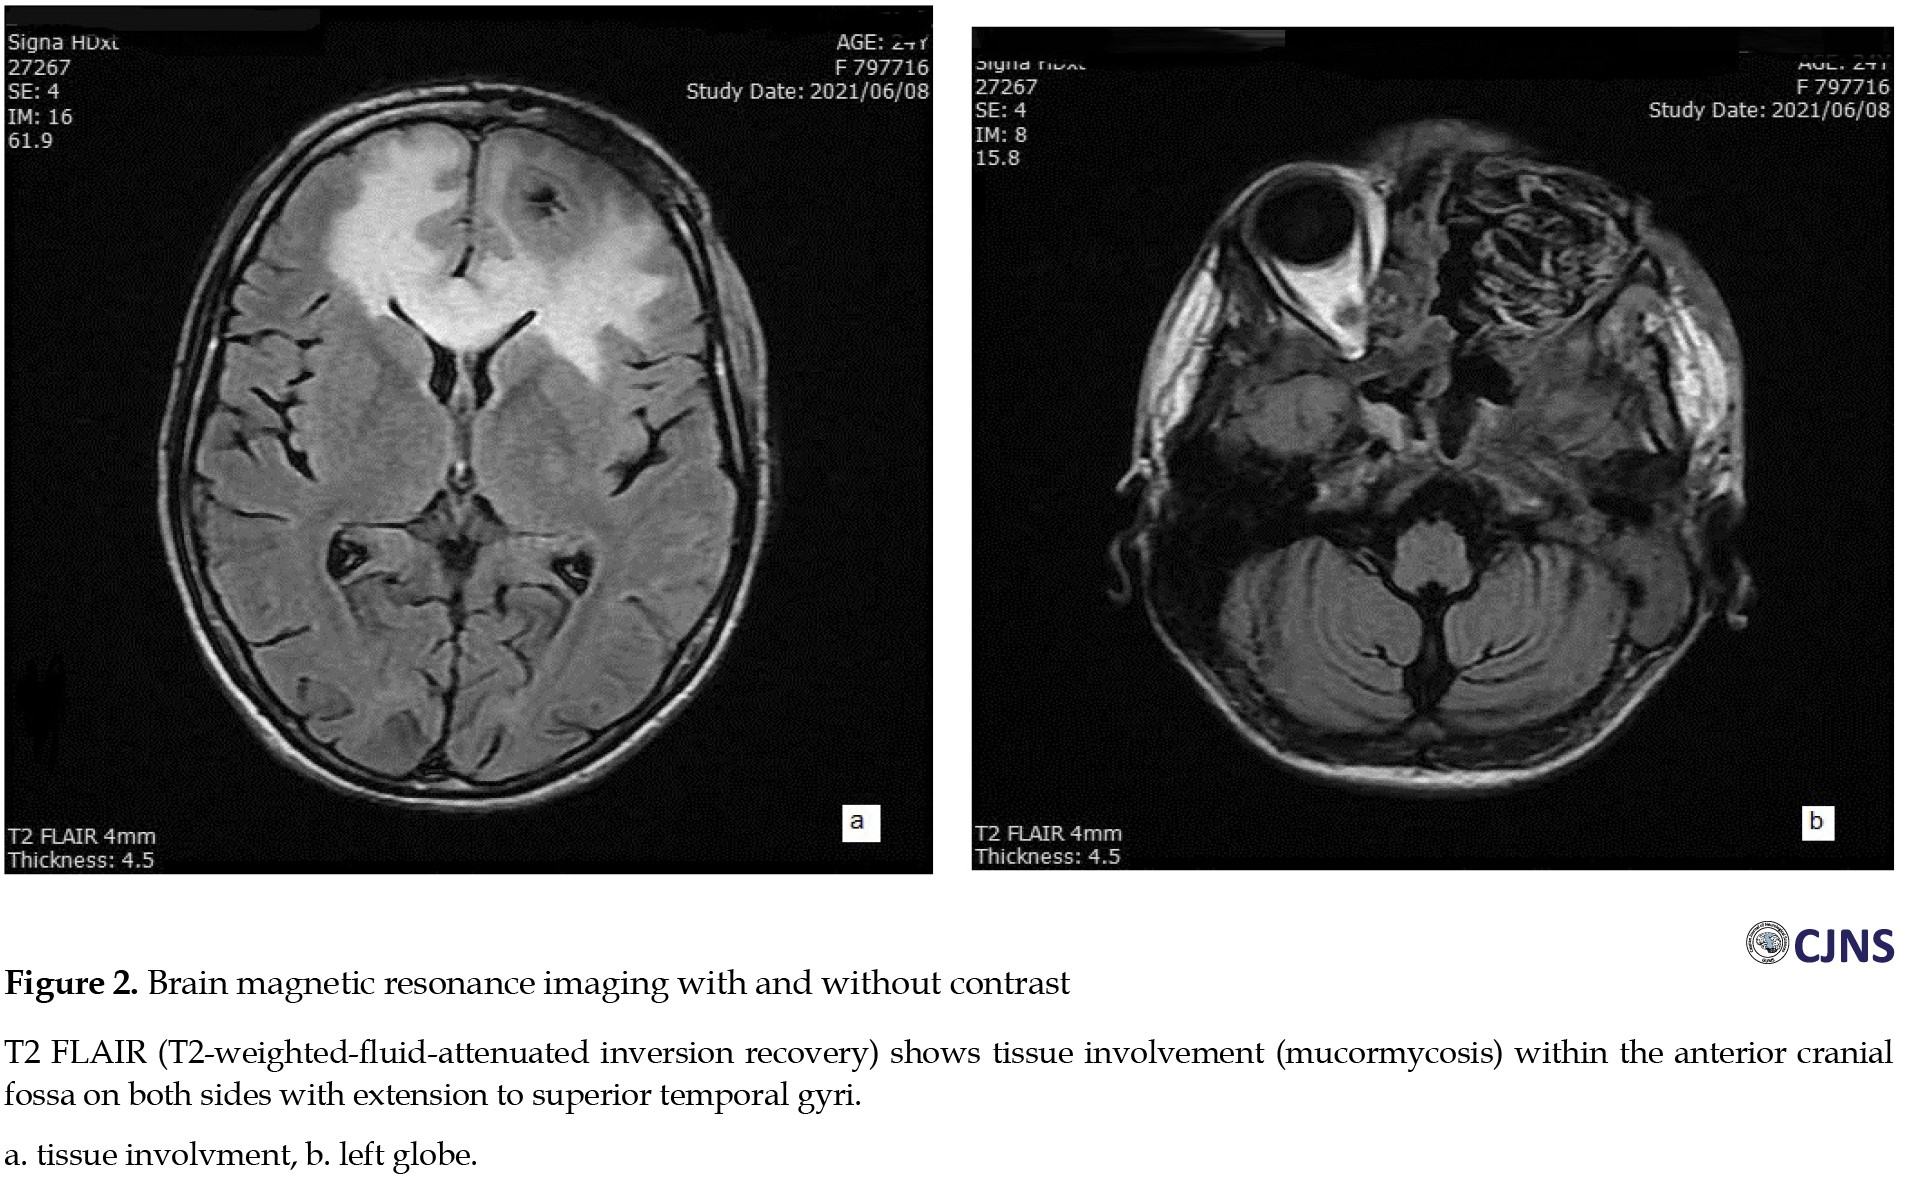

The patient was transferred to another university hospital for surgical debridement of hard and soft palates destroyed by progressive mucormycosis. A brain magnetic resonance imaging (MRI) performed on the second week of admission revealed hypodense areas in the frontal lobe of the brain (

Figure 2).